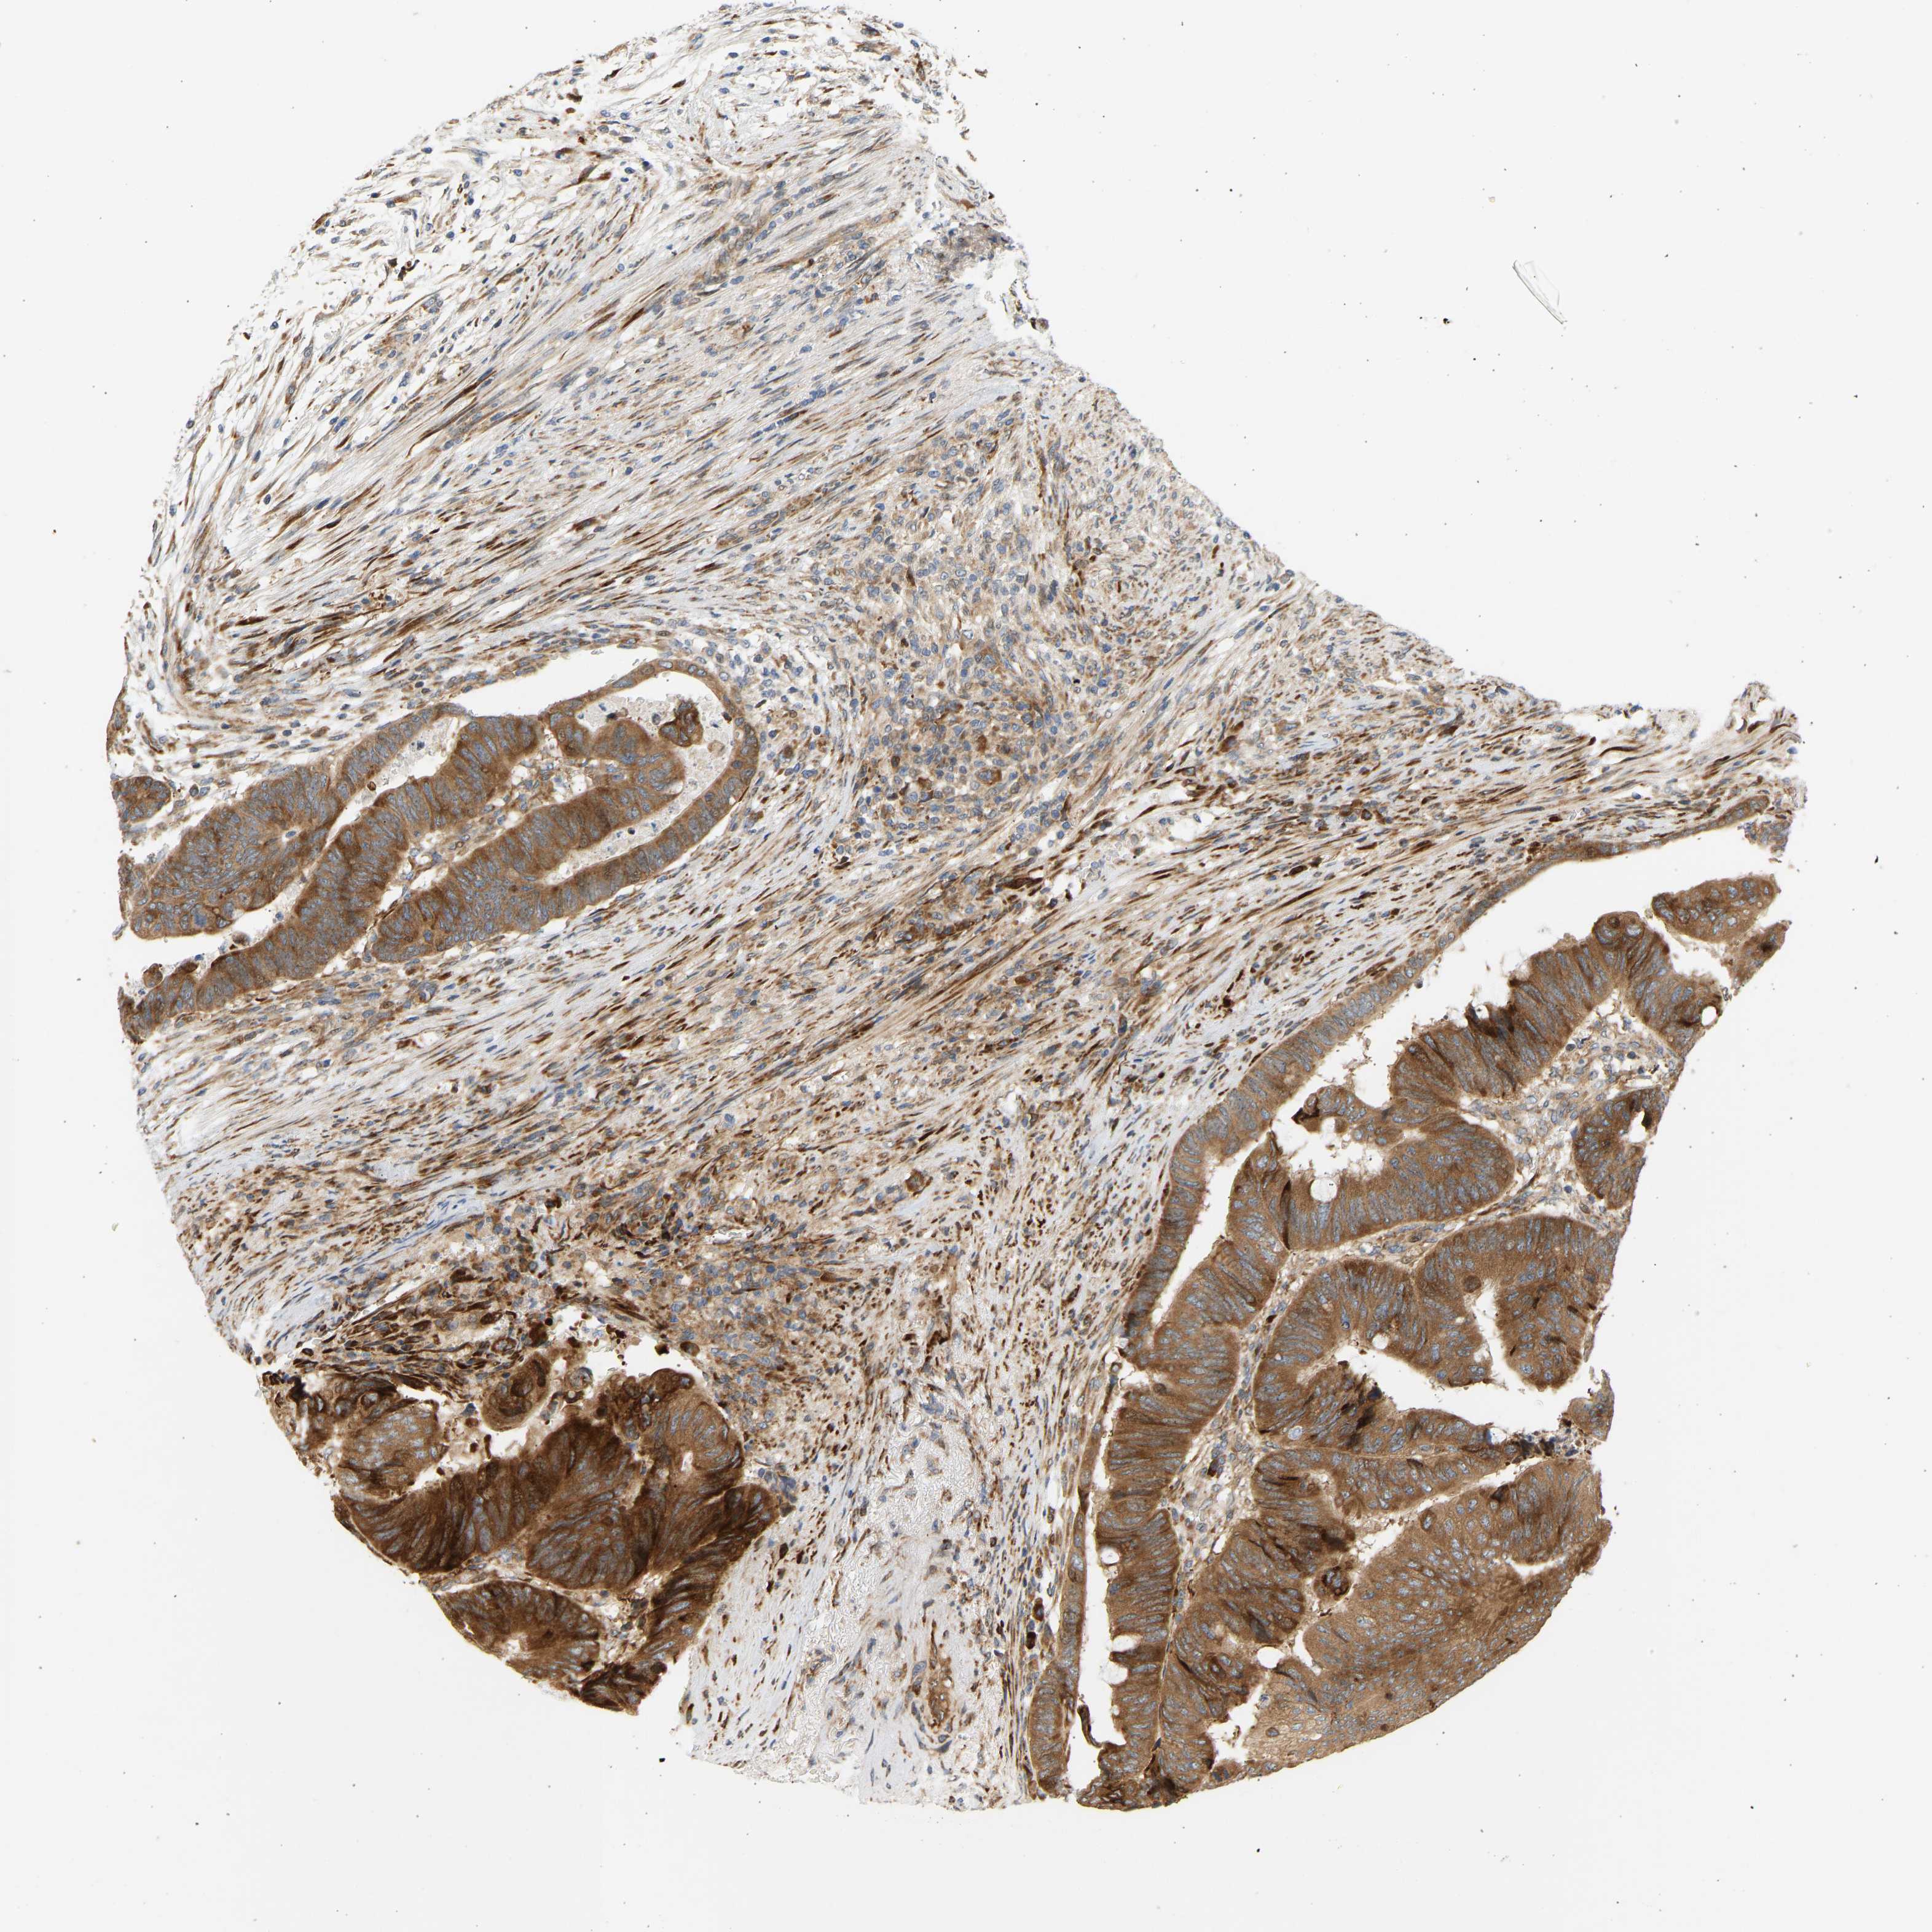

CANCER COLORECTAL CANCER Show tissue menu

ANTIBODIES

AND

VALIDATION